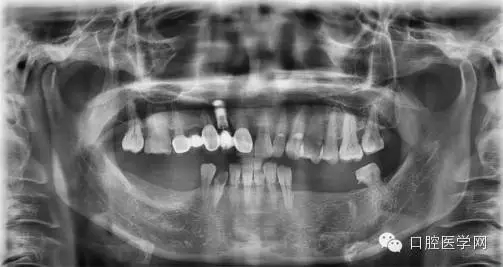

全景片檢查

下頜尖牙雙根管的治療

主訴:患者由于右下前牙折斷要求修復(fù)

現(xiàn)病史:患者由于大部分牙齒缺失而來(lái)就診,部分牙齒已經(jīng)種植,另外的缺失牙位也分期會(huì)處理。